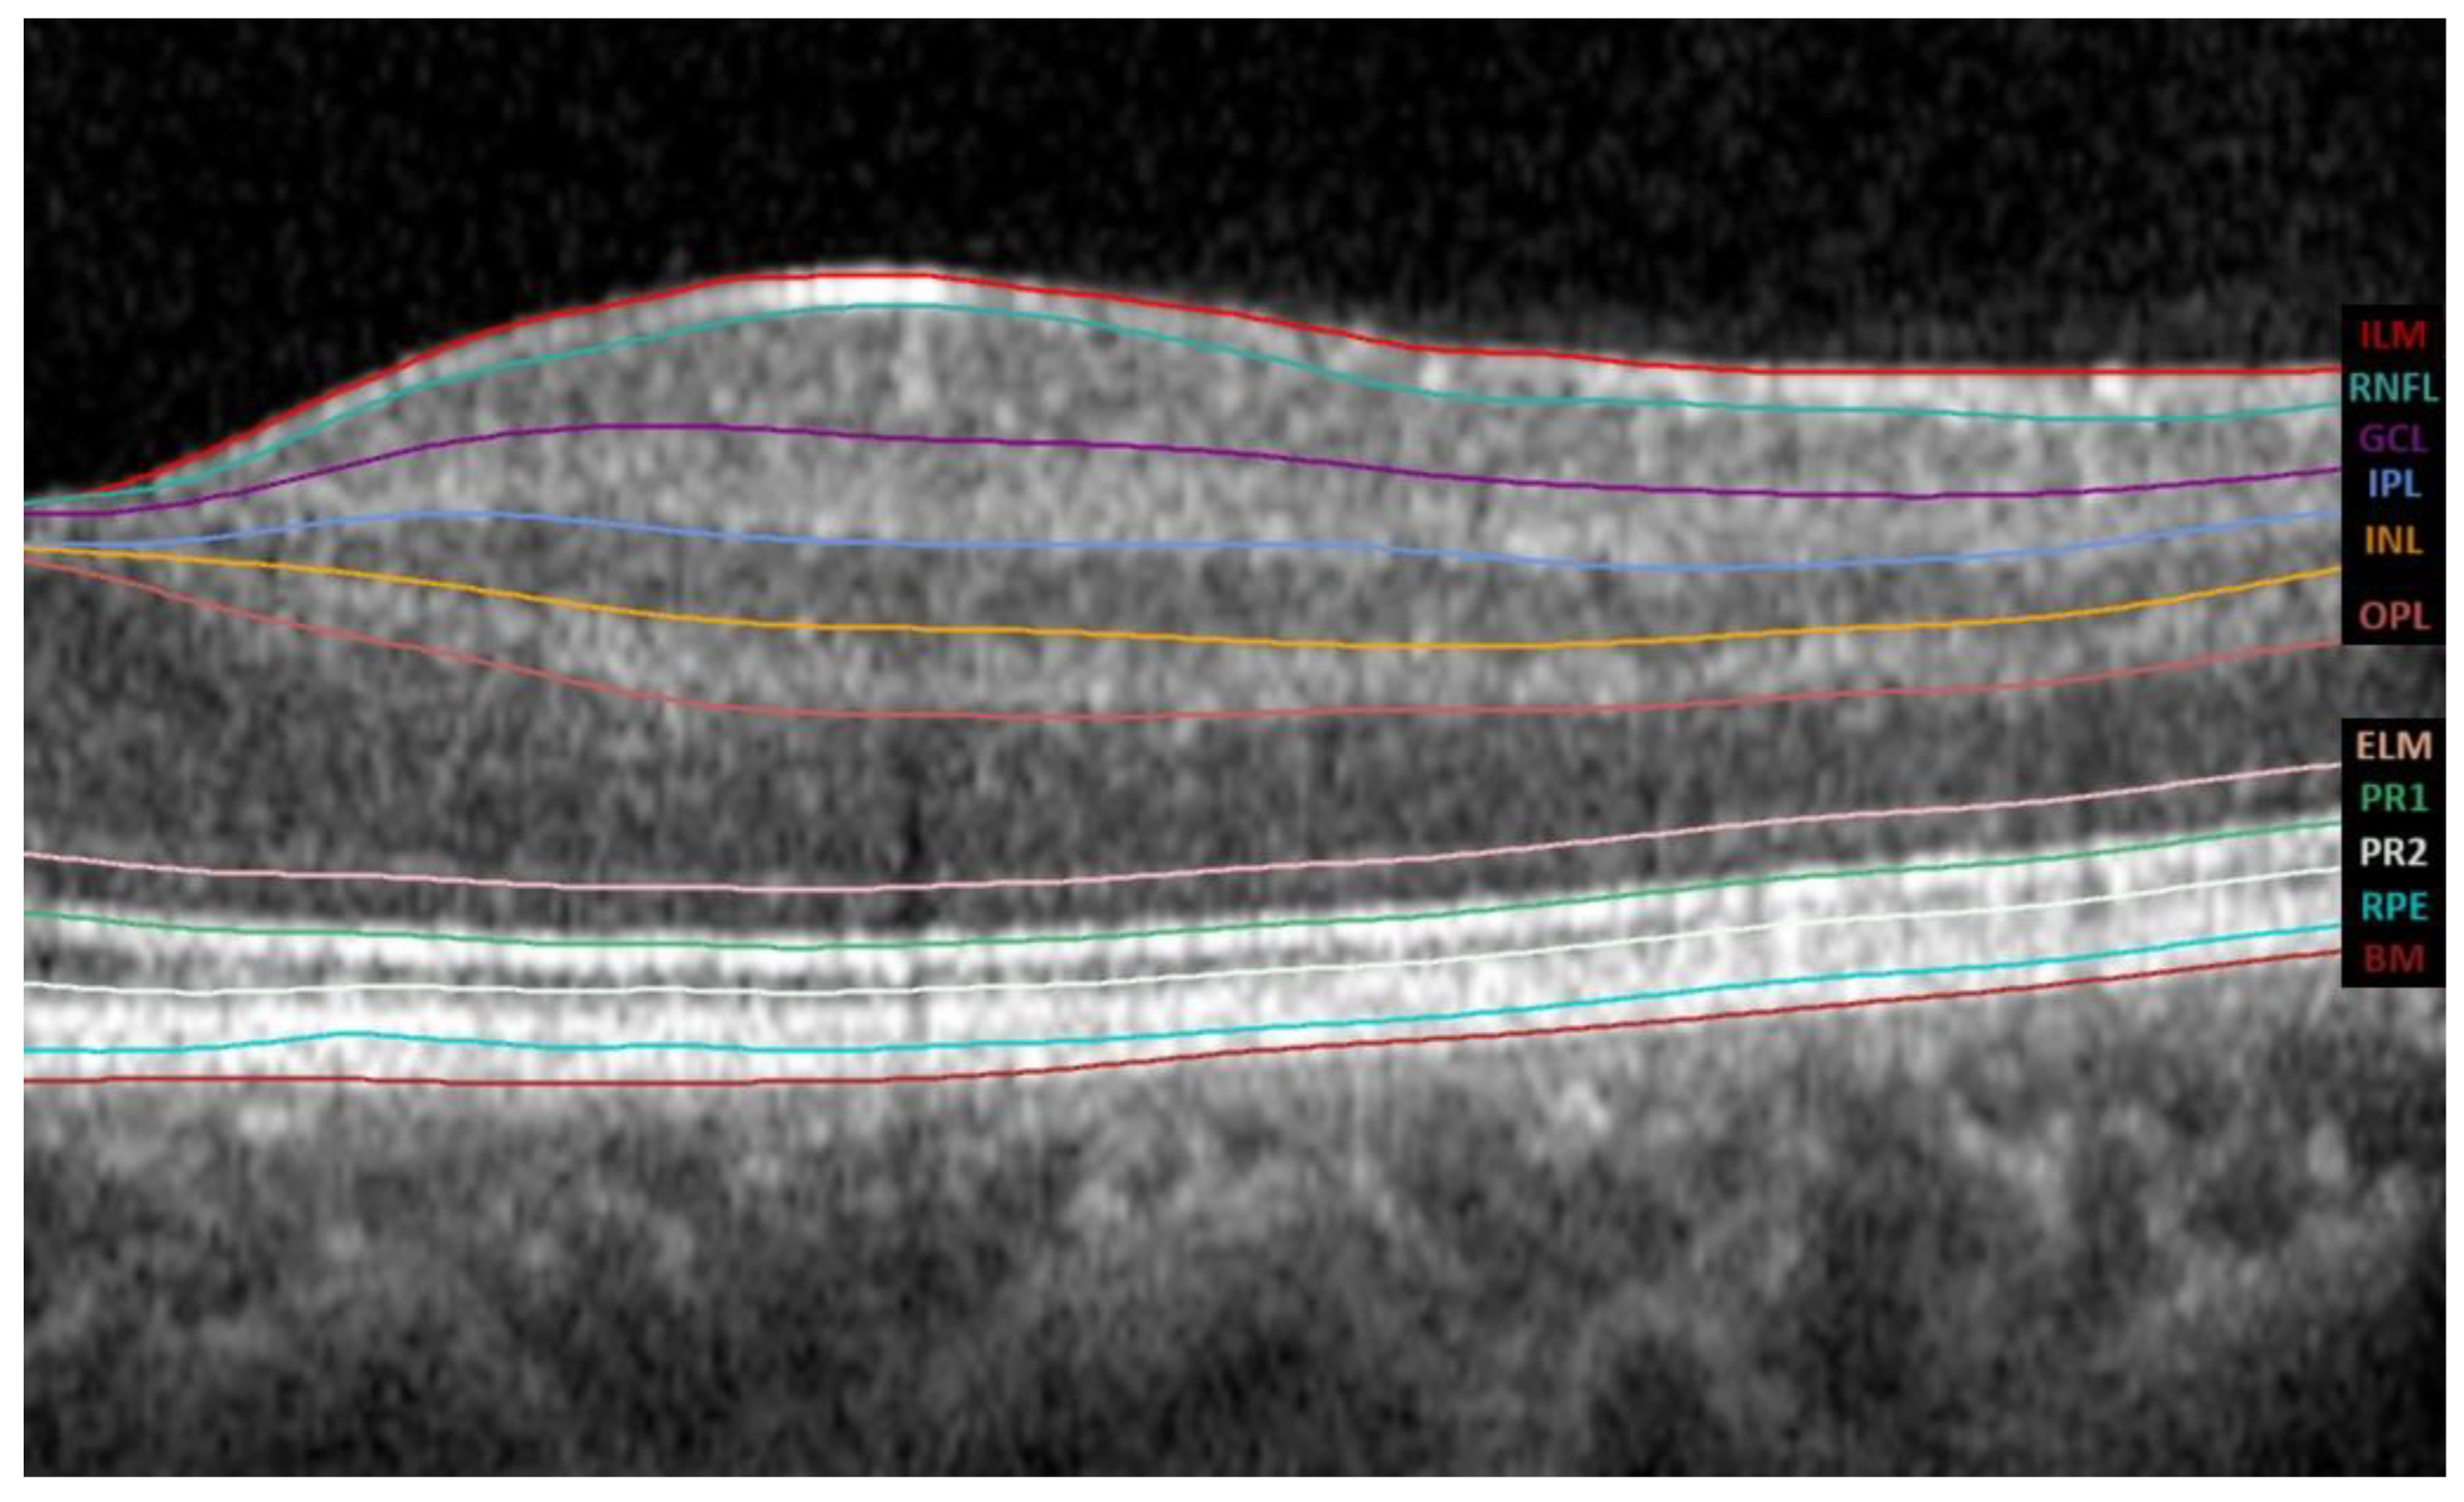

The Spectralis SD-OCT software version 6.8.1.0. automatically segments the retina into the IRL and ORL. IRL extends from the inner limiting membrane (ILM) to the external limiting membrane (ELM), whereas ORL extends from the ELM to the Bruch membrane (BM). It further divides the IRL into 6 layers, the RNFL, the ganglion cell layer (GCL), the inner plexiform layer (IPL), the inner nuclear layer (INL), the outer plexiform layer (OPL), and the outer nuclear layer (ONL), as shown in Figure 2.

Figure 2.

The tomographic profile obtained by Spectralis SD-OCT; the automatic segmentation was performed using its software version 6.8.1.0. The abbreviations for all layers of the automated macular segmentation provided by Spectralis SD-OCT software can be found on the right margin. Abbreviations: ILM, inner limiting membrane; RNFL, retinal nerve fiber layer; GCL, ganglion cell layer; IPL, inner plexiform layer; INL, inner nuclear layer; OPL, outer plexiform layer; ELM, external limiting membrane; PR1, photoreceptor inner segments; PR2, photoreceptor outer segments; RPE, retinal pigment epithelium; BM, Bruch membrane.